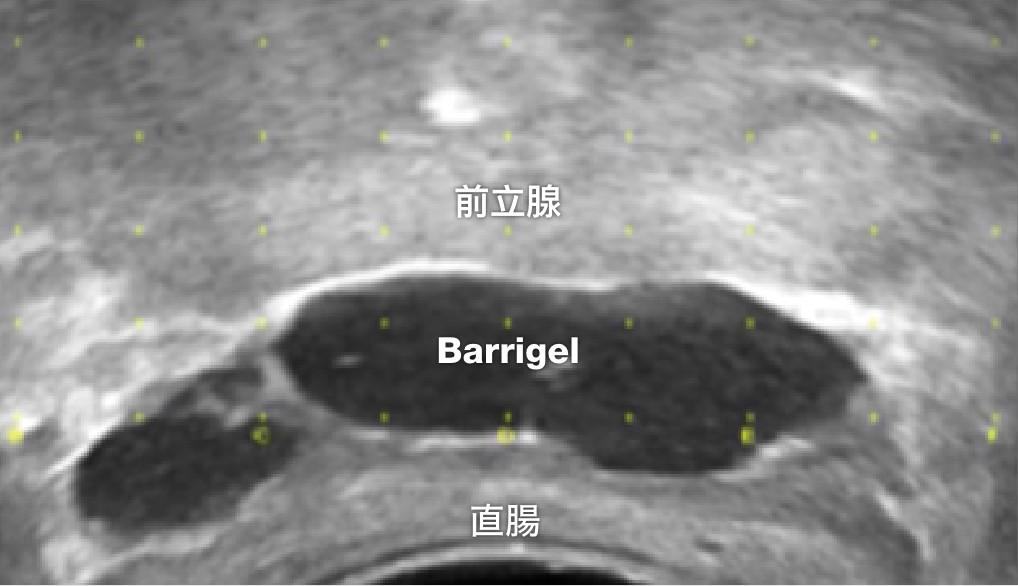

TRUS 画像

TRUS画像提供:Prof Michael Chao, MBBS (Hons), FRANZCR, AFRACMA, DMedSc, Radiation Oncologist; Victoria, Australia

TRUS画像提供:Neil F. Mariados, MD

Radiation Oncologist; New York, United States